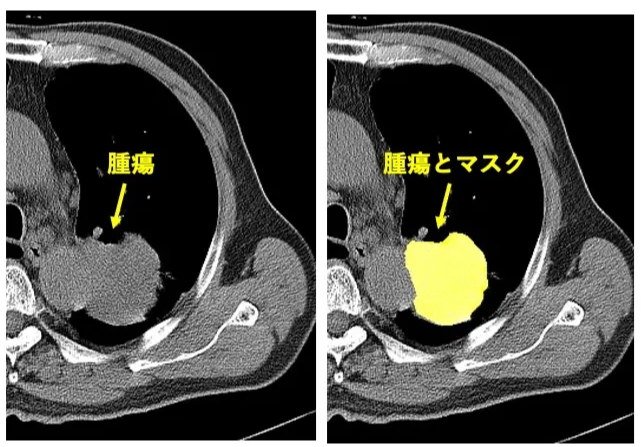

腫瘍領域の抽出には、Vision Transformerを利用した医用画像のセグメンテーションモデルMedSAM2(4)を使用しました。本モデルは Segment Anything Model 2 を医用画像向けに拡張した手法であり、1スライスに数点のプロンプトを入力し領域抽出をすると、他のスライスまで自動抽出が可能です(Fig.2)。実行は、Google Colabratory上のPython環境(GPU: NVIDIA Tesla T4)で行いました。

腫瘍の領域抽出は、専門医による手動設定が一般的ですが、大量の画像に対してスライスごとに領域を設定するため作業負荷の大きさが課題です。本検討では、MedSAM2を使うことで領域抽出の省力化を図りました。具体的には、1画像に約8スライスの腫瘍領域があったことから、1/8の作業時間短縮ができました。さらに、手作業による領域の描画を数点のプロンプト入力に代替することで、1/2以上の時間短縮ができたと考えられ、計1/16以上の時間短縮ができたと考えます。

現在のスライスの画像と領域抽出で取得したマスク画像の特徴を基に、次のスライスを推論する。

領域抽出処理の流れは以下の通りです:

- CT画像をスライス単位で読み込む

- 1スライスの腫瘍領域に点プロンプトを入力

- MedSAM2を適用し、他のスライスにおいて領域抽出およびバイナリマスク生成

- 得られたマスクをradiomics特徴量の抽出に使用

この際、階調は縦隔条件(window level=l40、window width=400)で固定し、MedSAM2による推論をしました。また、マスク画像と元画像で座標系を一致させました。